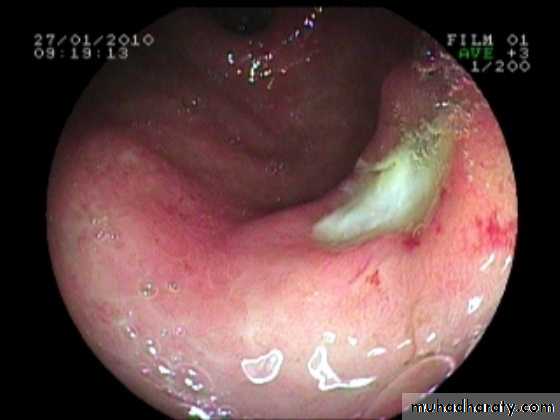

Dysphagia : Investigations

Esophageal dysphagia disorders cause dysphagia by obstructing the lumen or by affecting motility. Patients with esophageal disease complain of food ‘sticking’ after swallowing.

Dysphagia is defined as difficulty in swallowing.It may coexist with heartburn or vomiting but should be distinguished

from both globus sensation (in which anxious people feel a lump in the throat without organic cause) and odynophagia (pain during swallowing, usually from gastro-esophageal reflux or candidiasis).